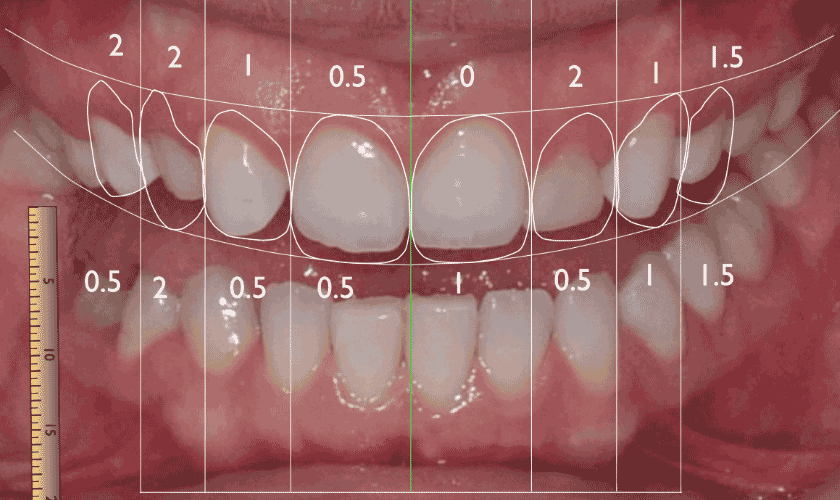

Phân tích màu sắc, tỉ lệ chuẩn giữa môi, nướu và răng

- Bước 3: Nghiên cứu, đo đạc và phân tích nụ cười thông qua dữ liệu trên phần mềm máy tính

- Bước 4: Thiết kế nụ cười phù hợp với kết cấu và tỷ lệ gương mặt